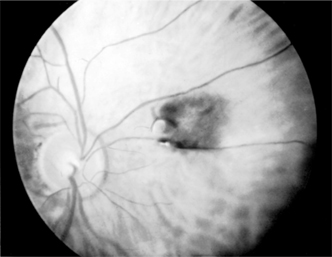

Figure 7-8

Figure 7-8: Nevus of the choroid. (Photo by Diane Beeston.)

Nevi (Figures 7-7 and 7-8) are usually flat lesions with or without pigment lying in the stroma of the tissue. On the anterior surface of the iris, they may be noted as iris "freckles." Posteriorly in the choroid, one may see flat pigmented areas. Large choroidal nevi are difficult to differentiate from malignant melanomas. Their flat appearance and especially their lack of growth on repeat serial examinations are important in the differential diagnosis from malignant melanoma.

Because of the difficulties in differentiation from malignant melanomas, fundus photographs or careful line drawings should be made of all suspicious lesions. The elevation or thickness of these lesions can best be measured and documented by ultrasonography. Observations should be made periodically for changes.